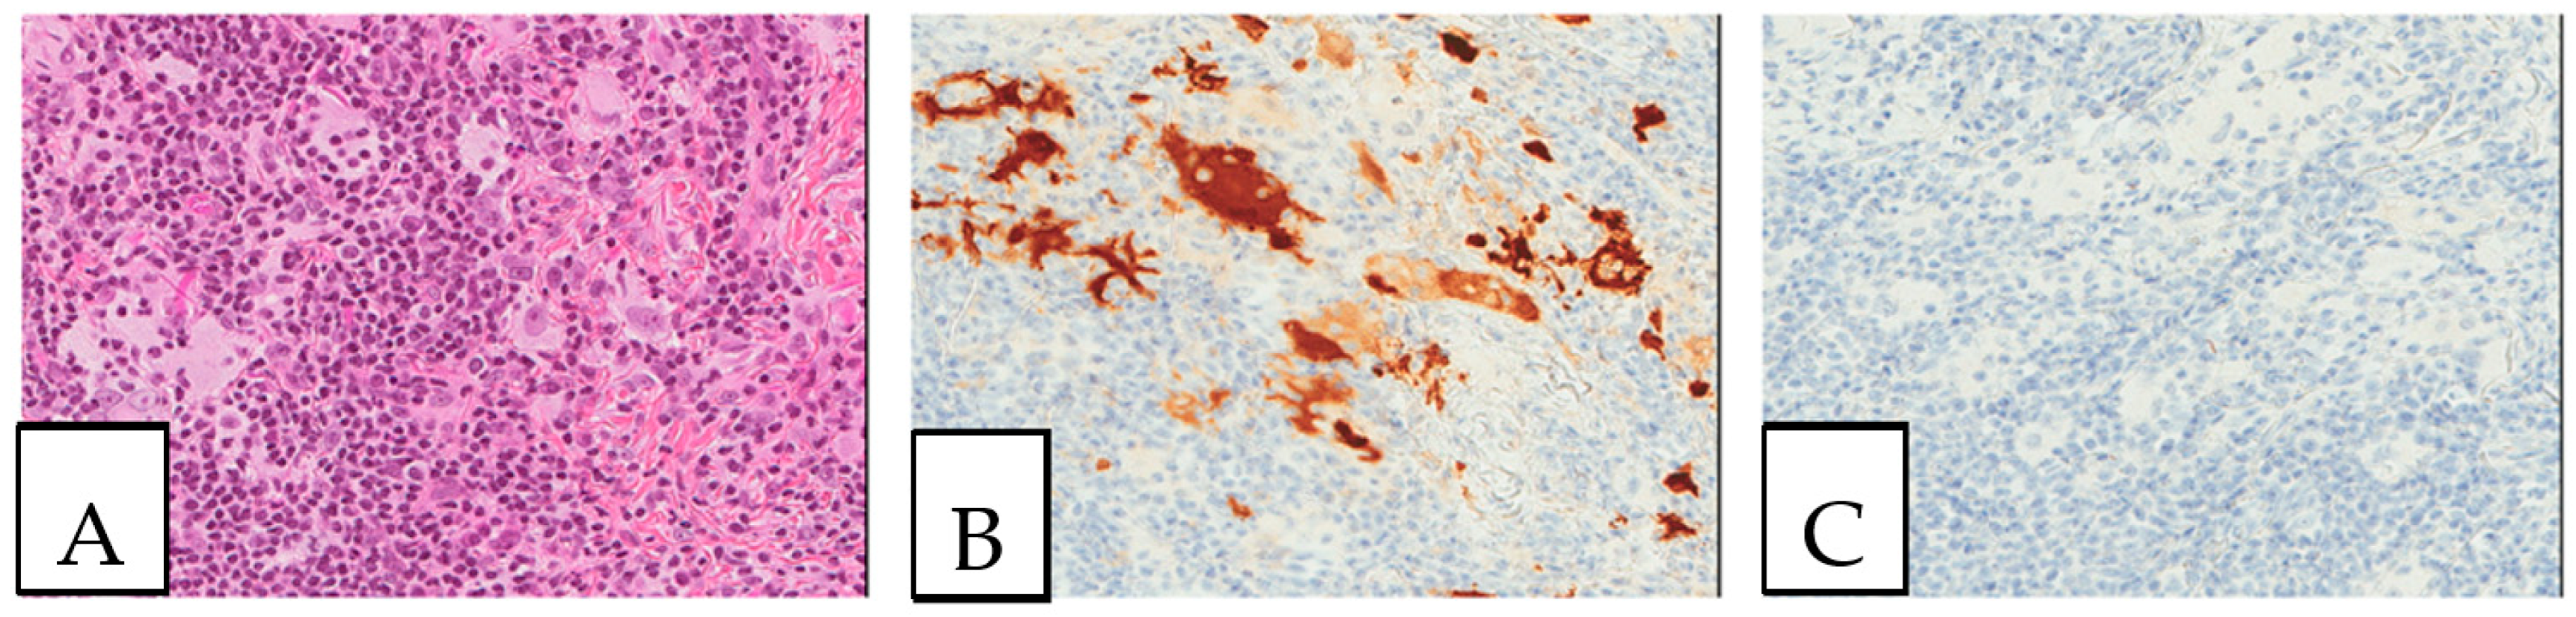

Langerhans cell histiocytosis is a multi-system disease of clonal origin, associated with RAS/MAPK pathway mutations, especially the BRAF V600E mutation, which presents morphologically with cleaved coffee bean-like cells in an eosinophil-rich background. The neoplastic cells are positive for anti-S100, CD1a, and langerin (Figure 5). Rosai Dorfman disease is a non-Langerhans cell histiocytosis (Figure 6), usually involving the lymph nodes and the skin, but can also show a disseminated form. It is characterized by histiocytic accumulation with an eosinophilic cytoplasm and, sometimes, cytoplasmic ingested inflammatory cells (emperipolesis).

Figure 5.

Langerhans cell histiocytosis. (A). Cutaneous Langerhans cell histiocytosis with characteristic coffee bean-like cells (B). CD1a-positive tumor cells. (C). S100-positive tumor cells. The patient was a young female adult presenting with multiple skin lesions, whose biopsy is shown here.

Figure 6.

Rosai Dorfman disease. (A). Cutaneous Rosai Dorfman disease showing histiocytes with an enlarged eosinophilic cytoplasm with engulfed inflammatory cells (emperipolesis). (B). S100-positive lesional cells. (C). CD1a-negative lesional cells. This biopsy was performed on a 64-year-old-female patient presenting with pigmented lesions of the back suspicious of regressive melanoma.